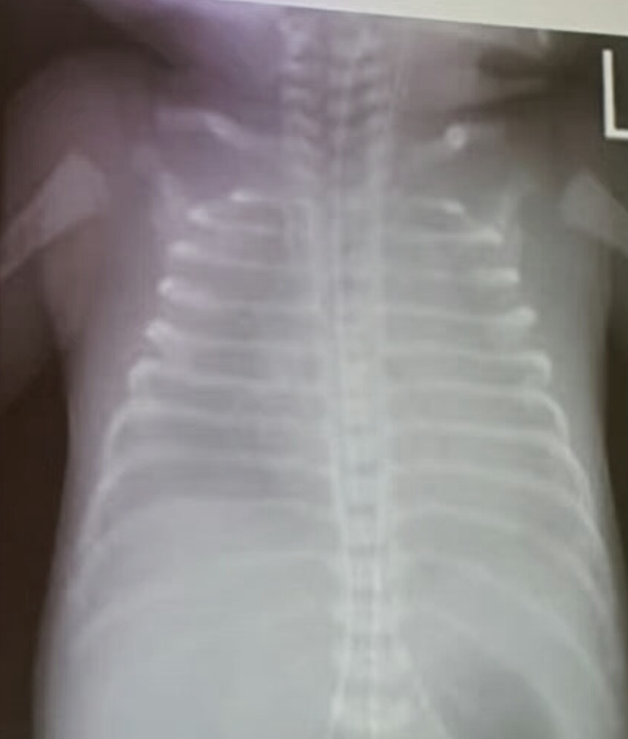

Case 29: Rickets

- Rickets rosary on sides of chest X-ray may be child abuse